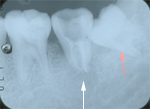

4.4ヵ月後

2ヶ月たって,腫れは1/3程度に小さくはなりましたが、

ろう孔は消えません。

考えた末、この歯を抜いて、その奥の横向きに生えている

親知らずを移植してくることにしました。

(上の写真の赤矢印)